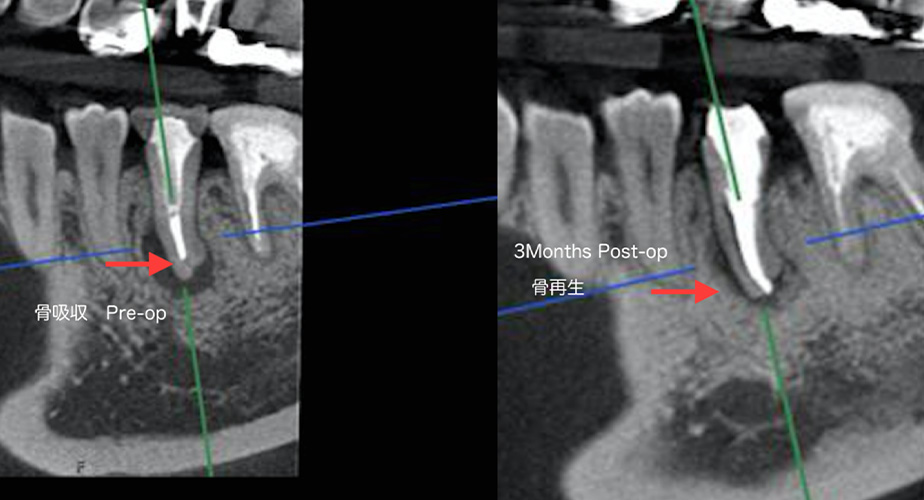

前医から「虫歯があるけれど経過観察し様子を見ましょう」と言われ、

不審に思い転医した

| 主訴 | 前医から「虫歯があるけれど経過観察し様子を見ましょう」と言われ、不審に思い転医した |

|---|---|

| 治療期間 | 根管治療3回、その後3か月治癒機関を見て、クラウン修復4回(全て1時間のアポイント) |

| 治療内容 | 根管内の感染が原因である根尖性歯周炎のため根の先に膿がたまっている状態で、根管治療により治癒した |

| 治療費 | 根管治療、修復治療(クラウン):¥290,000円 |

| 治療の リスク |

特にリスクなし |